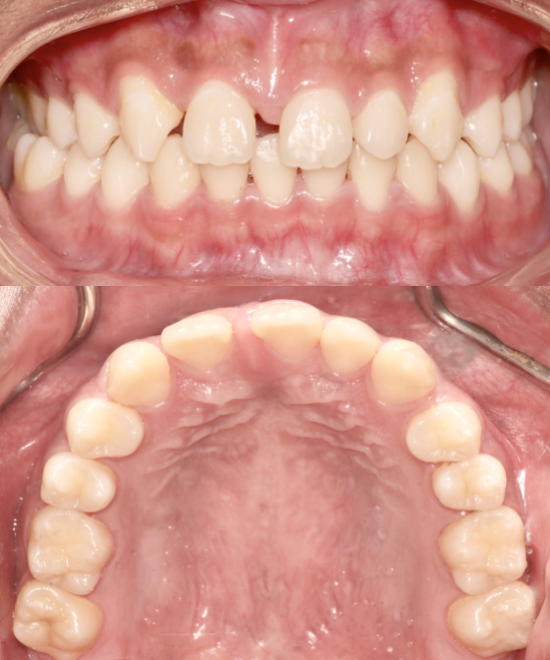

Before

After

BRACES - SPACE CLOSING

This patient presented with generalized spacing and misaligned teeth. Through comprehensive orthodontic treatment using braces, we successfully closed all spaces and aligned the teeth into an ideal arch form. A fixed lower retainer was placed to maintain long-term stability. The result is a healthier, more confident smile with improved function and aesthetics.